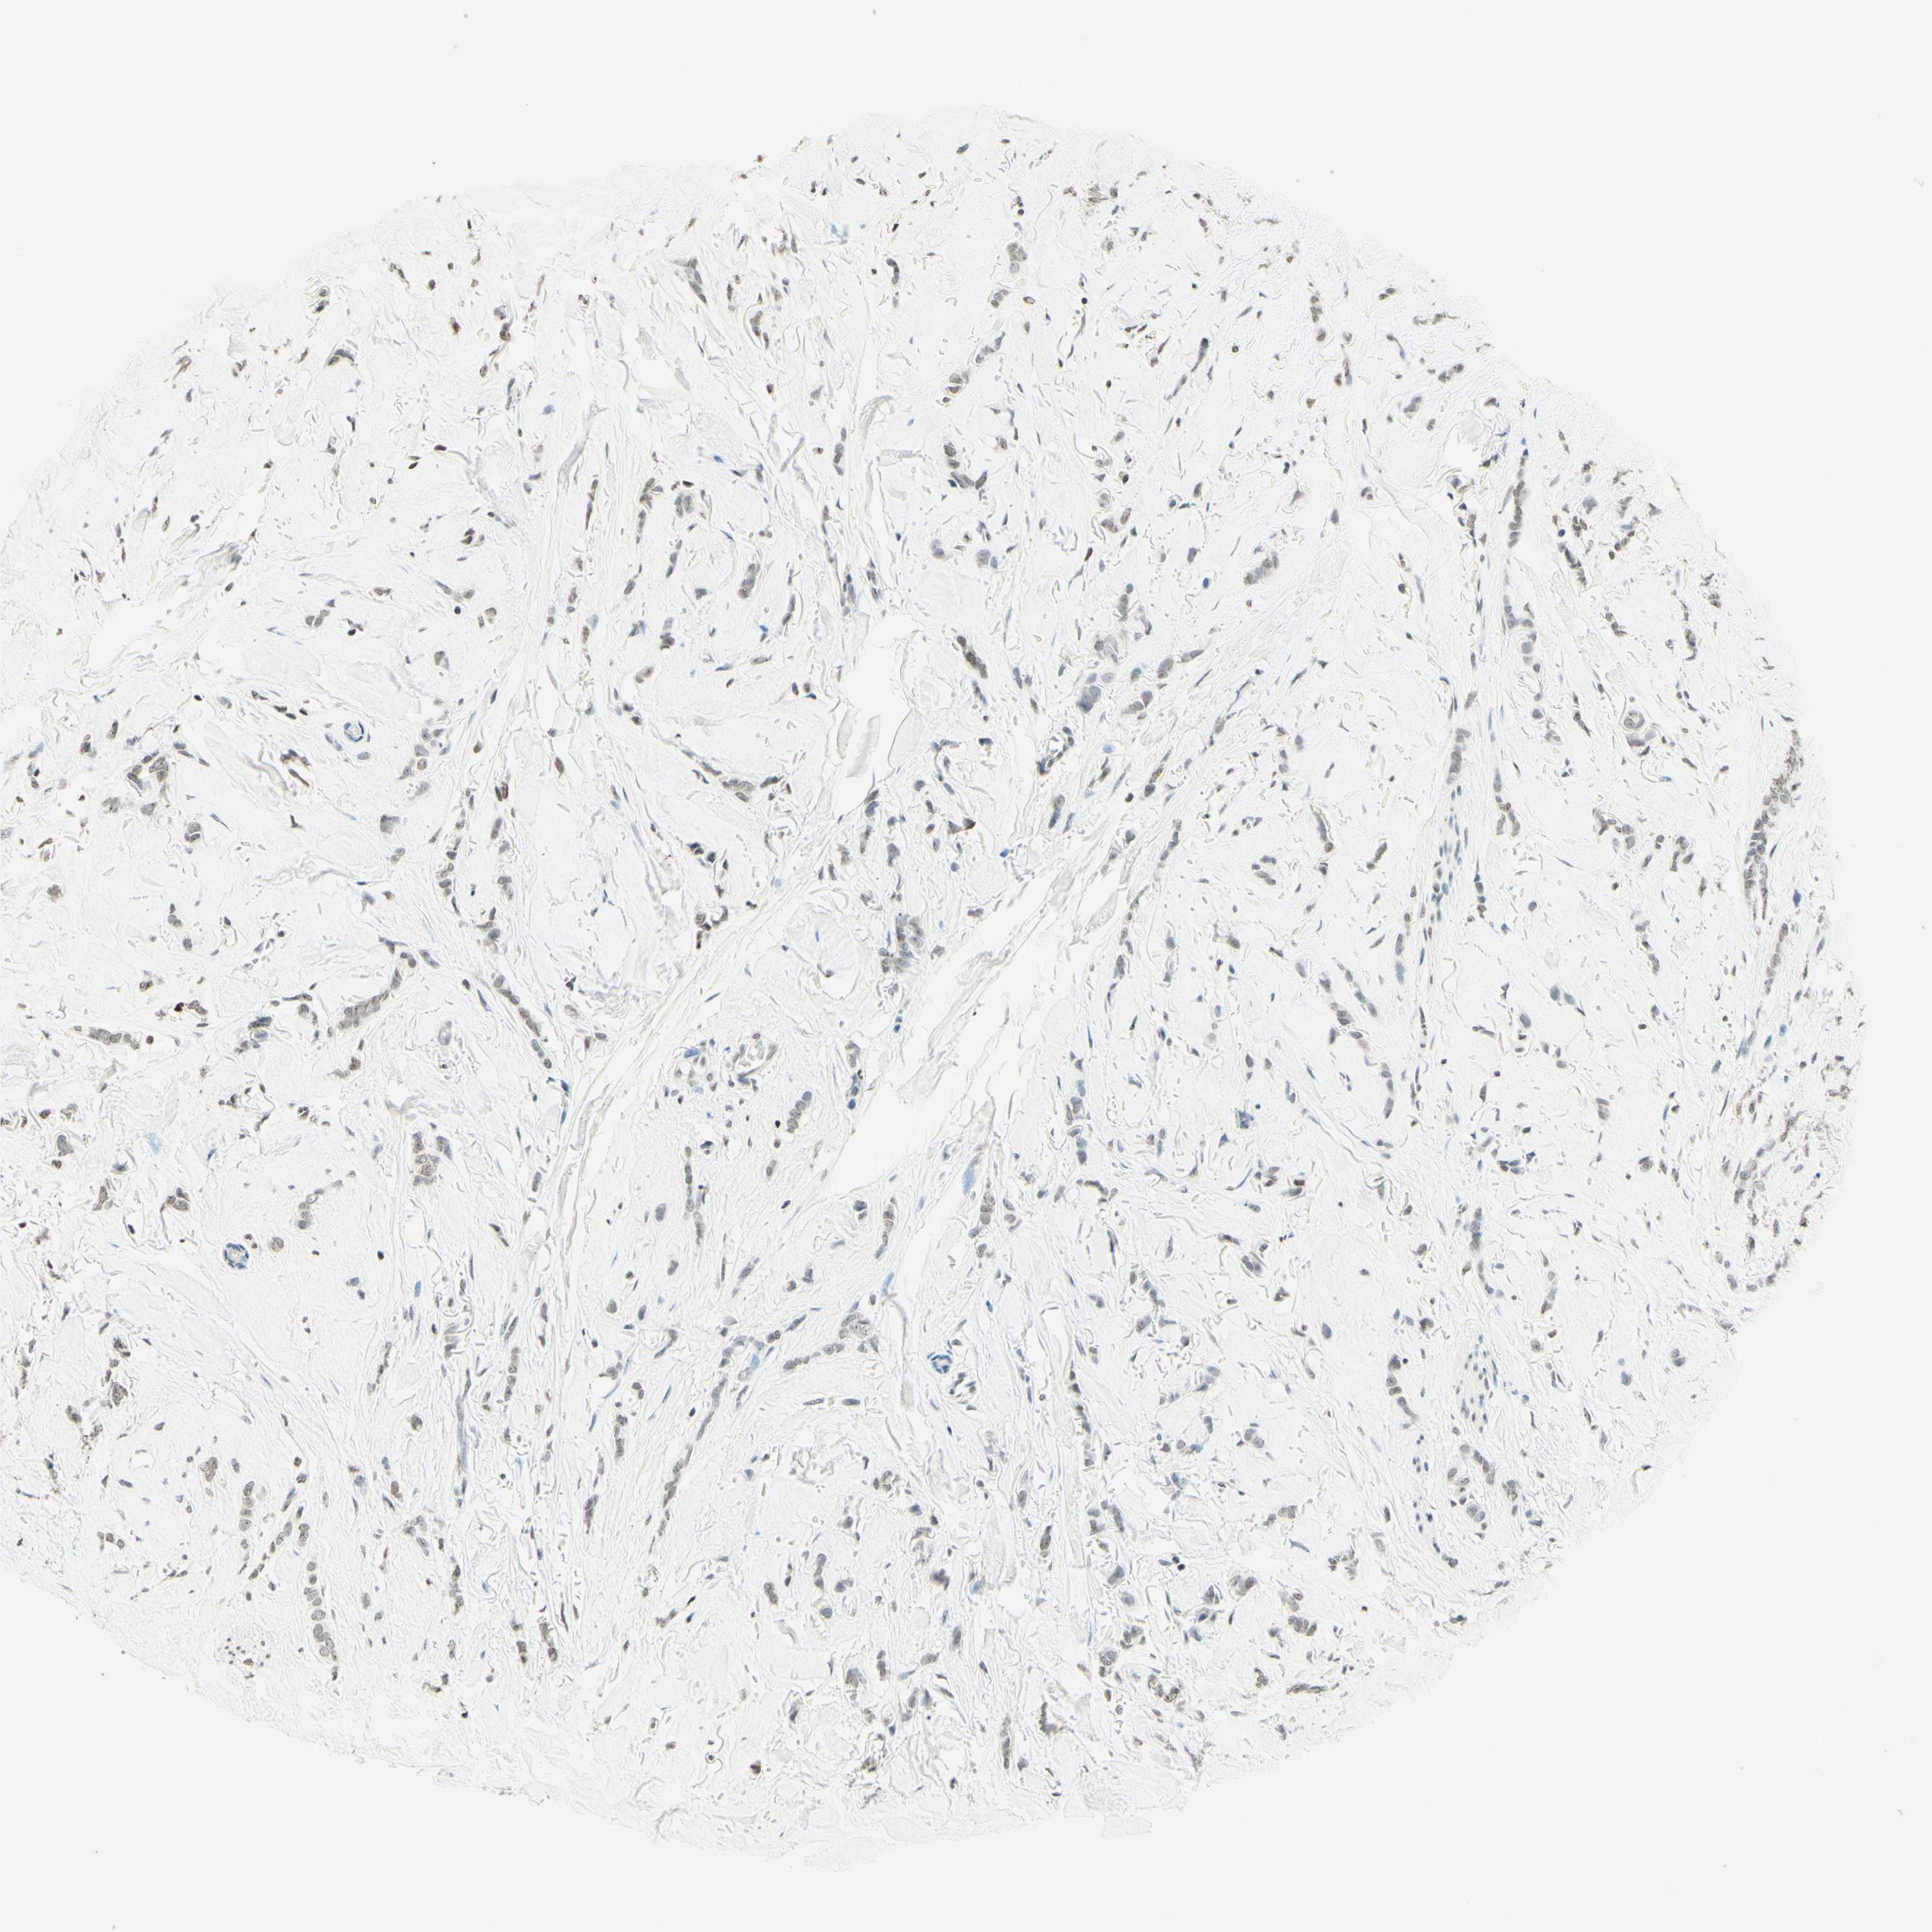

BRCA TCGA BRCA VALIDATION PROTEIN EXPRESSION

ANTIBODIES

AND

VALIDATION